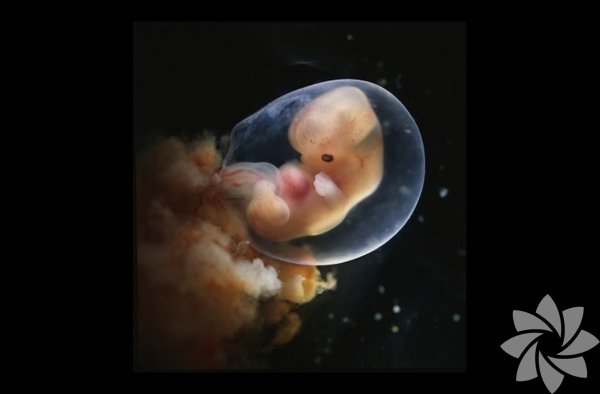

6. hafta. Artık kollar, bacaklar ve baş belirginleşti. Plasenta da bebekle birlikte büyüyor.

7. hafta